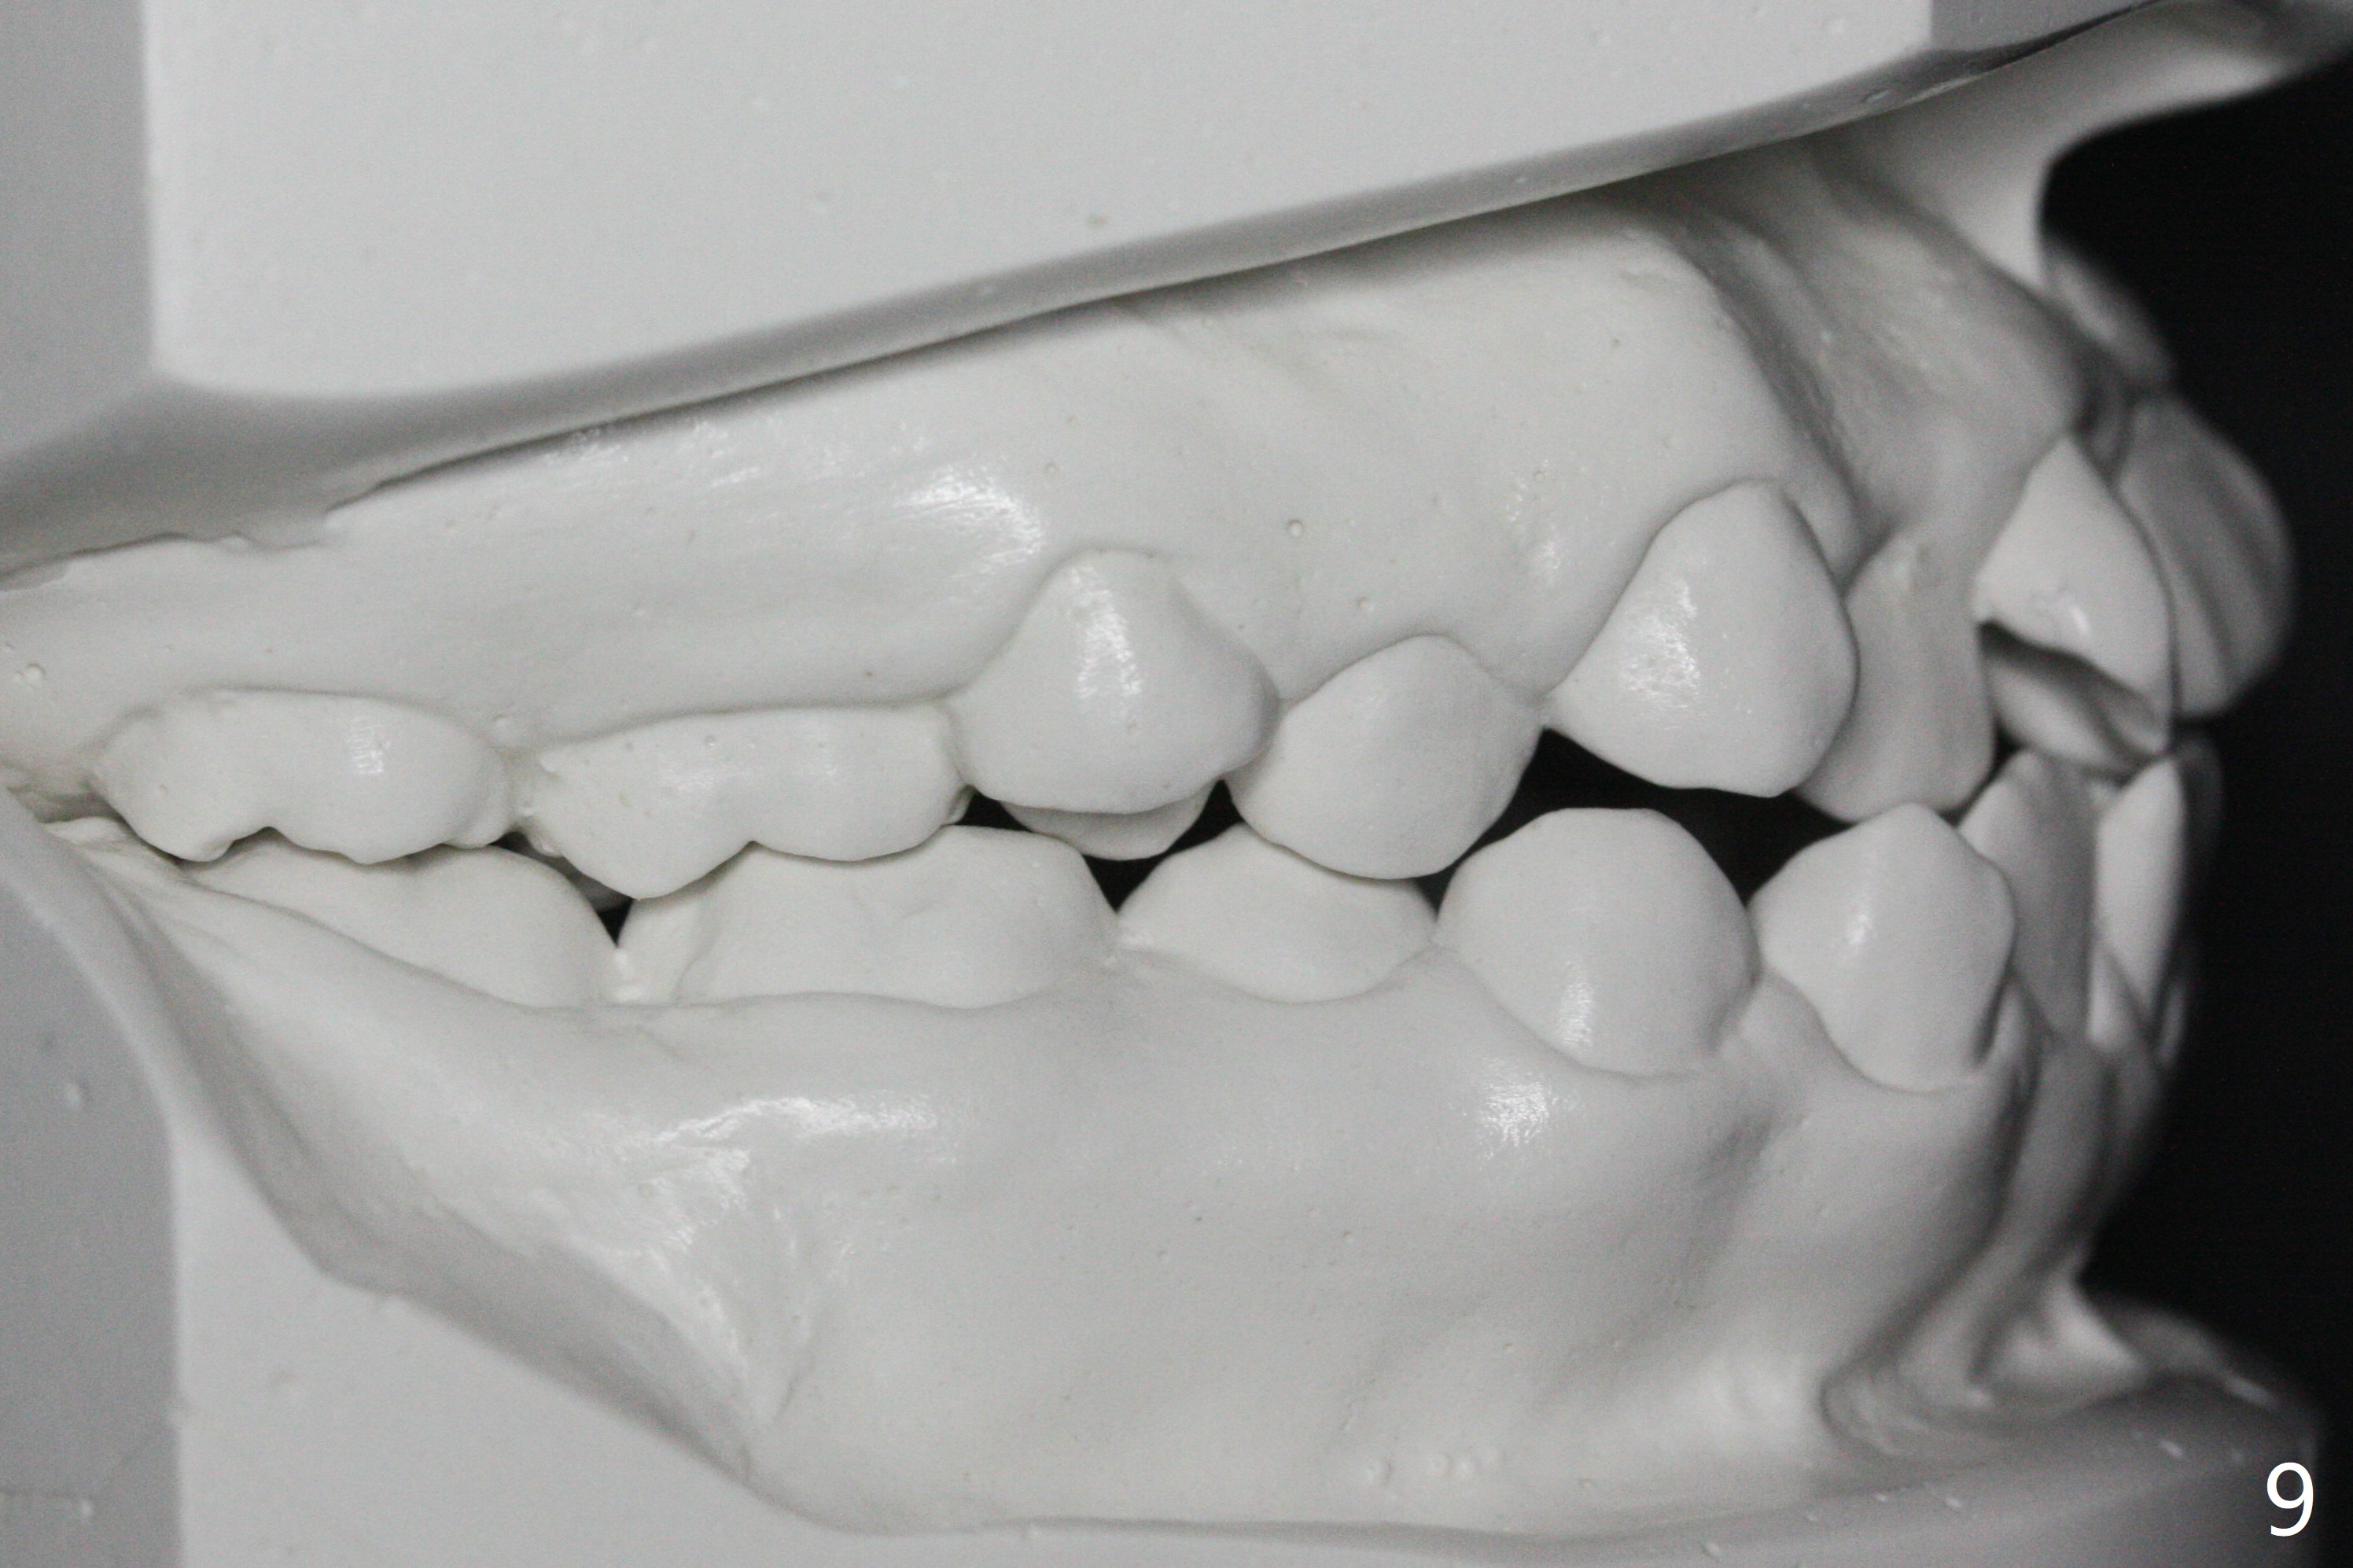

A 14-year-old woman has convex facial profile (Fig.1-4) with the upper midline shifted to the left (Fig.2). Since the roots of the 1st bicuspids are short (Fig.5), extraction should be easy. U3 will be retracted distal early with intention to correct the upper midline. With Class I occlusion at the canines and the 1st molars and good initial interdigitation (Fig.6-11), orthodontic treatment should be rewarding. Because of severe crowding (tight contact, Fig.12,13), place separators after extraction and place bands and brackets a few days later. Cephalometric analysis (Fig.14) shows that SNB is greater than SNA (82.4 vs. 81.8 degree); after extraction, retract the lower anterior teeth prior to the upper ones. It is easy to place separators after extraction (Fig.16,17).